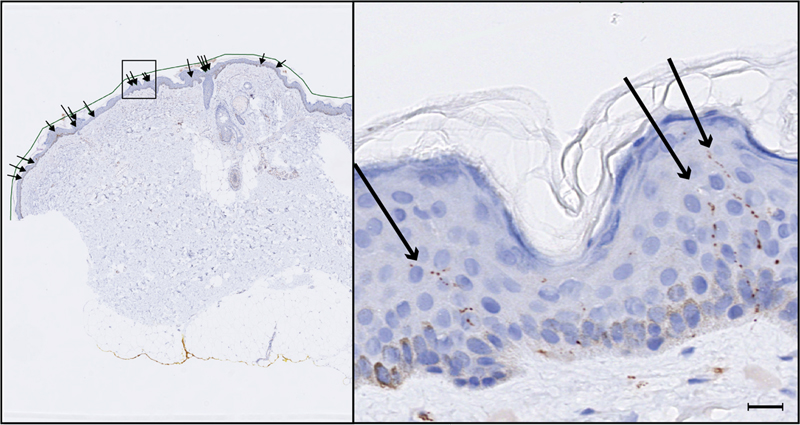

Figure 2. Assessment of IENFD in a 5 µm section

Intraepidermal nerve fiber density assessment illustrated in a 5 µm section stained with the PGP 9.5-antibody (overview to the left, close-up of the box-indicated portion to the right). Each counted nerve fiber (≥ 15 µm, see scale bar in the bottom right corner) is indicated by an arrow. Epidermal length was measured with an in-program device, see the green line (left).